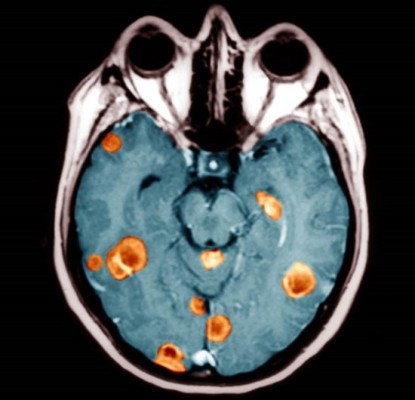

뇌종양은 뇌조직이나 뇌를 싸고 있는 막에서 발생된 종양과 머리뼈나 주변 구조물에서 멀리 떨어진 부위에서 뇌조직이나 뇌막으로 전이된 종양을 말합니다. 또, 뇌종양은 양성과 악성으로 나눌 수 있는데요. 양성 뇌종양은 성장속도가 느리고 주위 조직과의 경계가 뚜렷한 특성을 지니고 있습니다. 악성 뇌종양은 뇌암이라고도 말하며, 성장속도가 빠르고 주위 조직으로의 침투 능력이 강하여 주변의 정상 뇌조직을 빠른 속도로 파괴합니다.